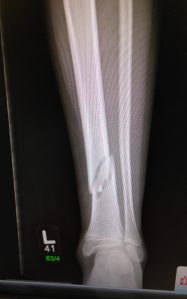

Within the hour, and obvious from the very first x-ray, we had our answer: M has a nasty spiral fracture to his left tibia. That has led to a full length leg cast from mid-thigh to toe, a considerable amount of tramadol, paracetamol and ibuprofen and an overnight stay for 2 on the surgical ward for observation. It’s been a difficult night as once again G has been sidelined whilst M heads into hospital, though this time the proximity to home has made it so much easier and she has been a superstar throughout. M’s pain has reached new levels of awful, though even then, as he lay sobbing in his hospital bed, he wouldn’t rate it as more than a 9, or possibly a 10, proving once again how accustomed to chronic pain he has become.

IMG_0302[1]The next few weeks are going to be tough and not just because of his broken leg. M is going to have to find a fortitude he’s never had before as he misses out on a much longed-for dream because of it. He is extremely disappointed, but courageously trying to take it in his stride, with the smile on his face we all know and love. I can see the hurt deep in his eyes, but we will hope that something even better comes from this disaster. What saddens me even more is that he really has been the victim in this situation. His broken leg is not due to careless or reckless behaviour on his part, but down to the action of another child. A child who probably has no idea of the physical damage to M’s body, let alone the other far-reaching consequences of his violence towards my child. I’m still reeling from the shock that a child of a similar age could cause such injury; disturbed that a family could leave without checking on his well-being and left hoping that my children don’t lose their beautiful skill of making friends of strangers wherever they are, even though the consequences can unbelievably be so devastating. I fear that this incident will leave an emotional scar on them both that will take a long time to heal.